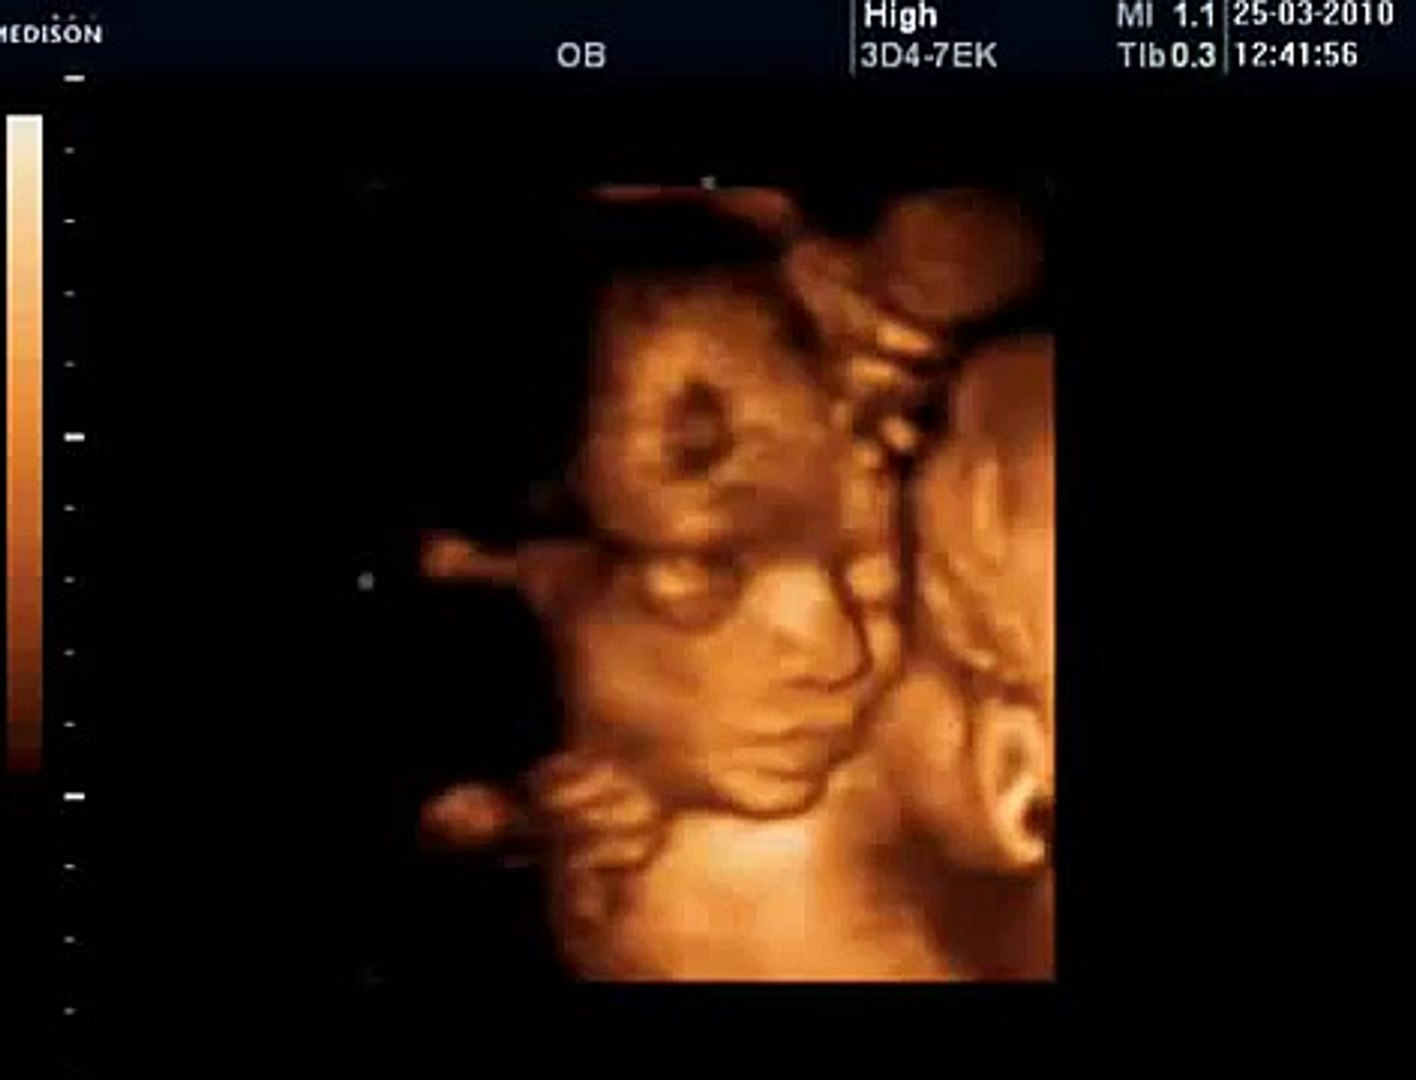

3d 4d Gorunumu 25 Hafta Gebelik Ultrason Goruntuleri Youtube